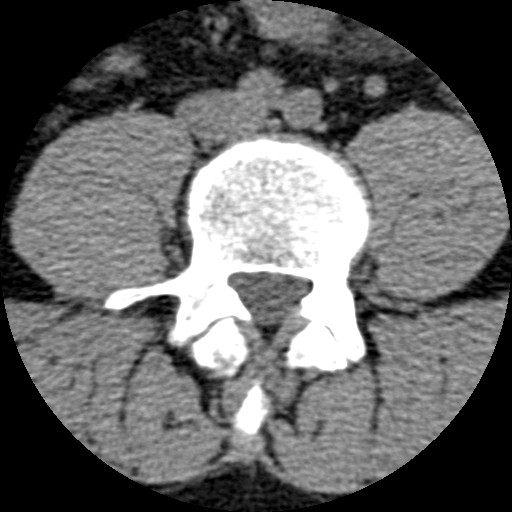

🔬 Séries Coluna (Partes Moles) + Osso (Janela Óssea) + Topograma — TAC Axial 3.0mm com contraste IV

⚕️ Diagnóstico HÉRNIA DISCAL L4-L5 — TAC pré-operatório para planeamento da discectomia (sem implantes)

Coluna (Partes Moles) 33 / 60

TAC lombar realizado em Janeiro de 2017 para diagnóstico pré-operatório de hérnia discal L4-L5 com radiculopatia. A cirurgia (discectomia L4-L5) foi realizada depois deste TAC, com remoção do fragmento de disco herniado sem colocação de implantes — sem fusão, sem parafusos, sem cage. Resultado cirúrgico: assintomático durante 6 anos, até ao acidente de 23/02/2023.

Patologia discal ao nível L4-L5 com protusão/extrusão discal que comprime a raíz nervosa L4 ou L5. O TAC em janela de partes moles pode mostrar o material discal herniado como uma densidade de tecidos moles no canal raquídeo ou foramen neural. A hérnia discal com radiculopatia foi a indicação cirúrgica para discectomia.

Lâminas e arco posterior completamente íntegros — a hemilaminotomia de acesso cirúrgico ainda não foi realizada. Este TAC documenta a anatomia óssea normal PRÉ-operatória. A cirurgia posterior irá criar um pequeno defeito laminar de acesso ao canal raquídeo para remoção da hérnia.

• ATENÇÃO — Contraste IV: Aorta e artérias ilíacas muito hiperdensas (branco intenso) — NÃO são implantes metálicos

• Nível L4-L5: Espaço discal com redução de altura + possível material herniado no canal

• Canal raquídeo: Avaliar compressão da saco tecal pela hérnia discal

• Foramens neurais L4-L5: Possível compressão foraminal da raíz L4 ou L5